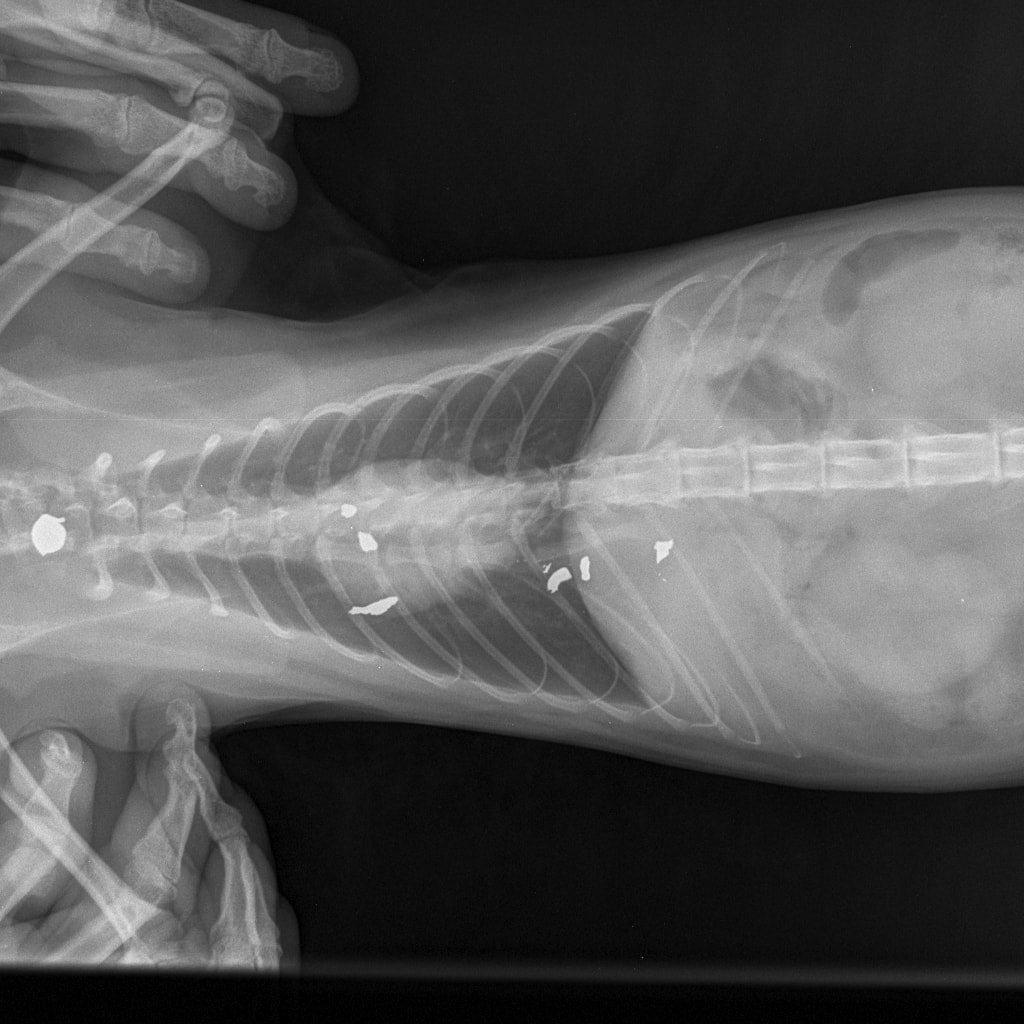

– Nikako ne mogu razumjeti da mi je netko namjerno ubio životinju. I to metkom koji se rasprsnuo u tijelu malene životinje što nije metak iz zračne puške. To se lijepo i vidi na rendgenskoj snimci koju smo obavili u Veterinarskoj ambulanti Majcan. U svakom slučaju, prijavili smo sve policiji koja će, iskreno se nadam, čim prije pronaći krivca – rekla nam je tužna vlasnica ubijene životinje.